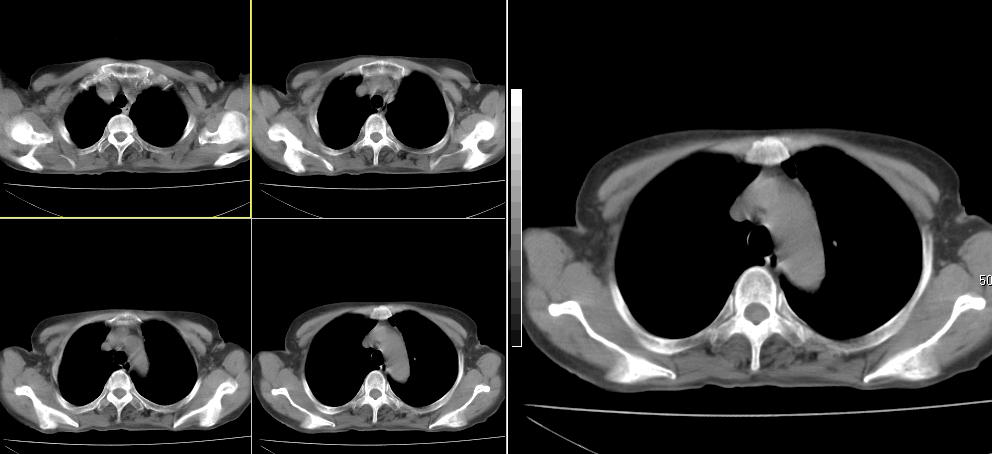

标题: CT26857:女,60岁,胃部不适前来就诊,不咳嗽,乏力,胸椎 [打印本页]

1、胸椎有骨质破坏伴周软组织,考虑胸椎转移。2、考虑左肺上叶尖后段支气管开口区周围型肺癌可能。

1、胸椎有骨质破坏伴周软组织,考虑胸椎转移。2、考虑左肺中央型肺癌可能。

支持中央型肺癌,胸椎转移。

左肺中央型肺癌,胸椎大致正常,必要时ect扫描